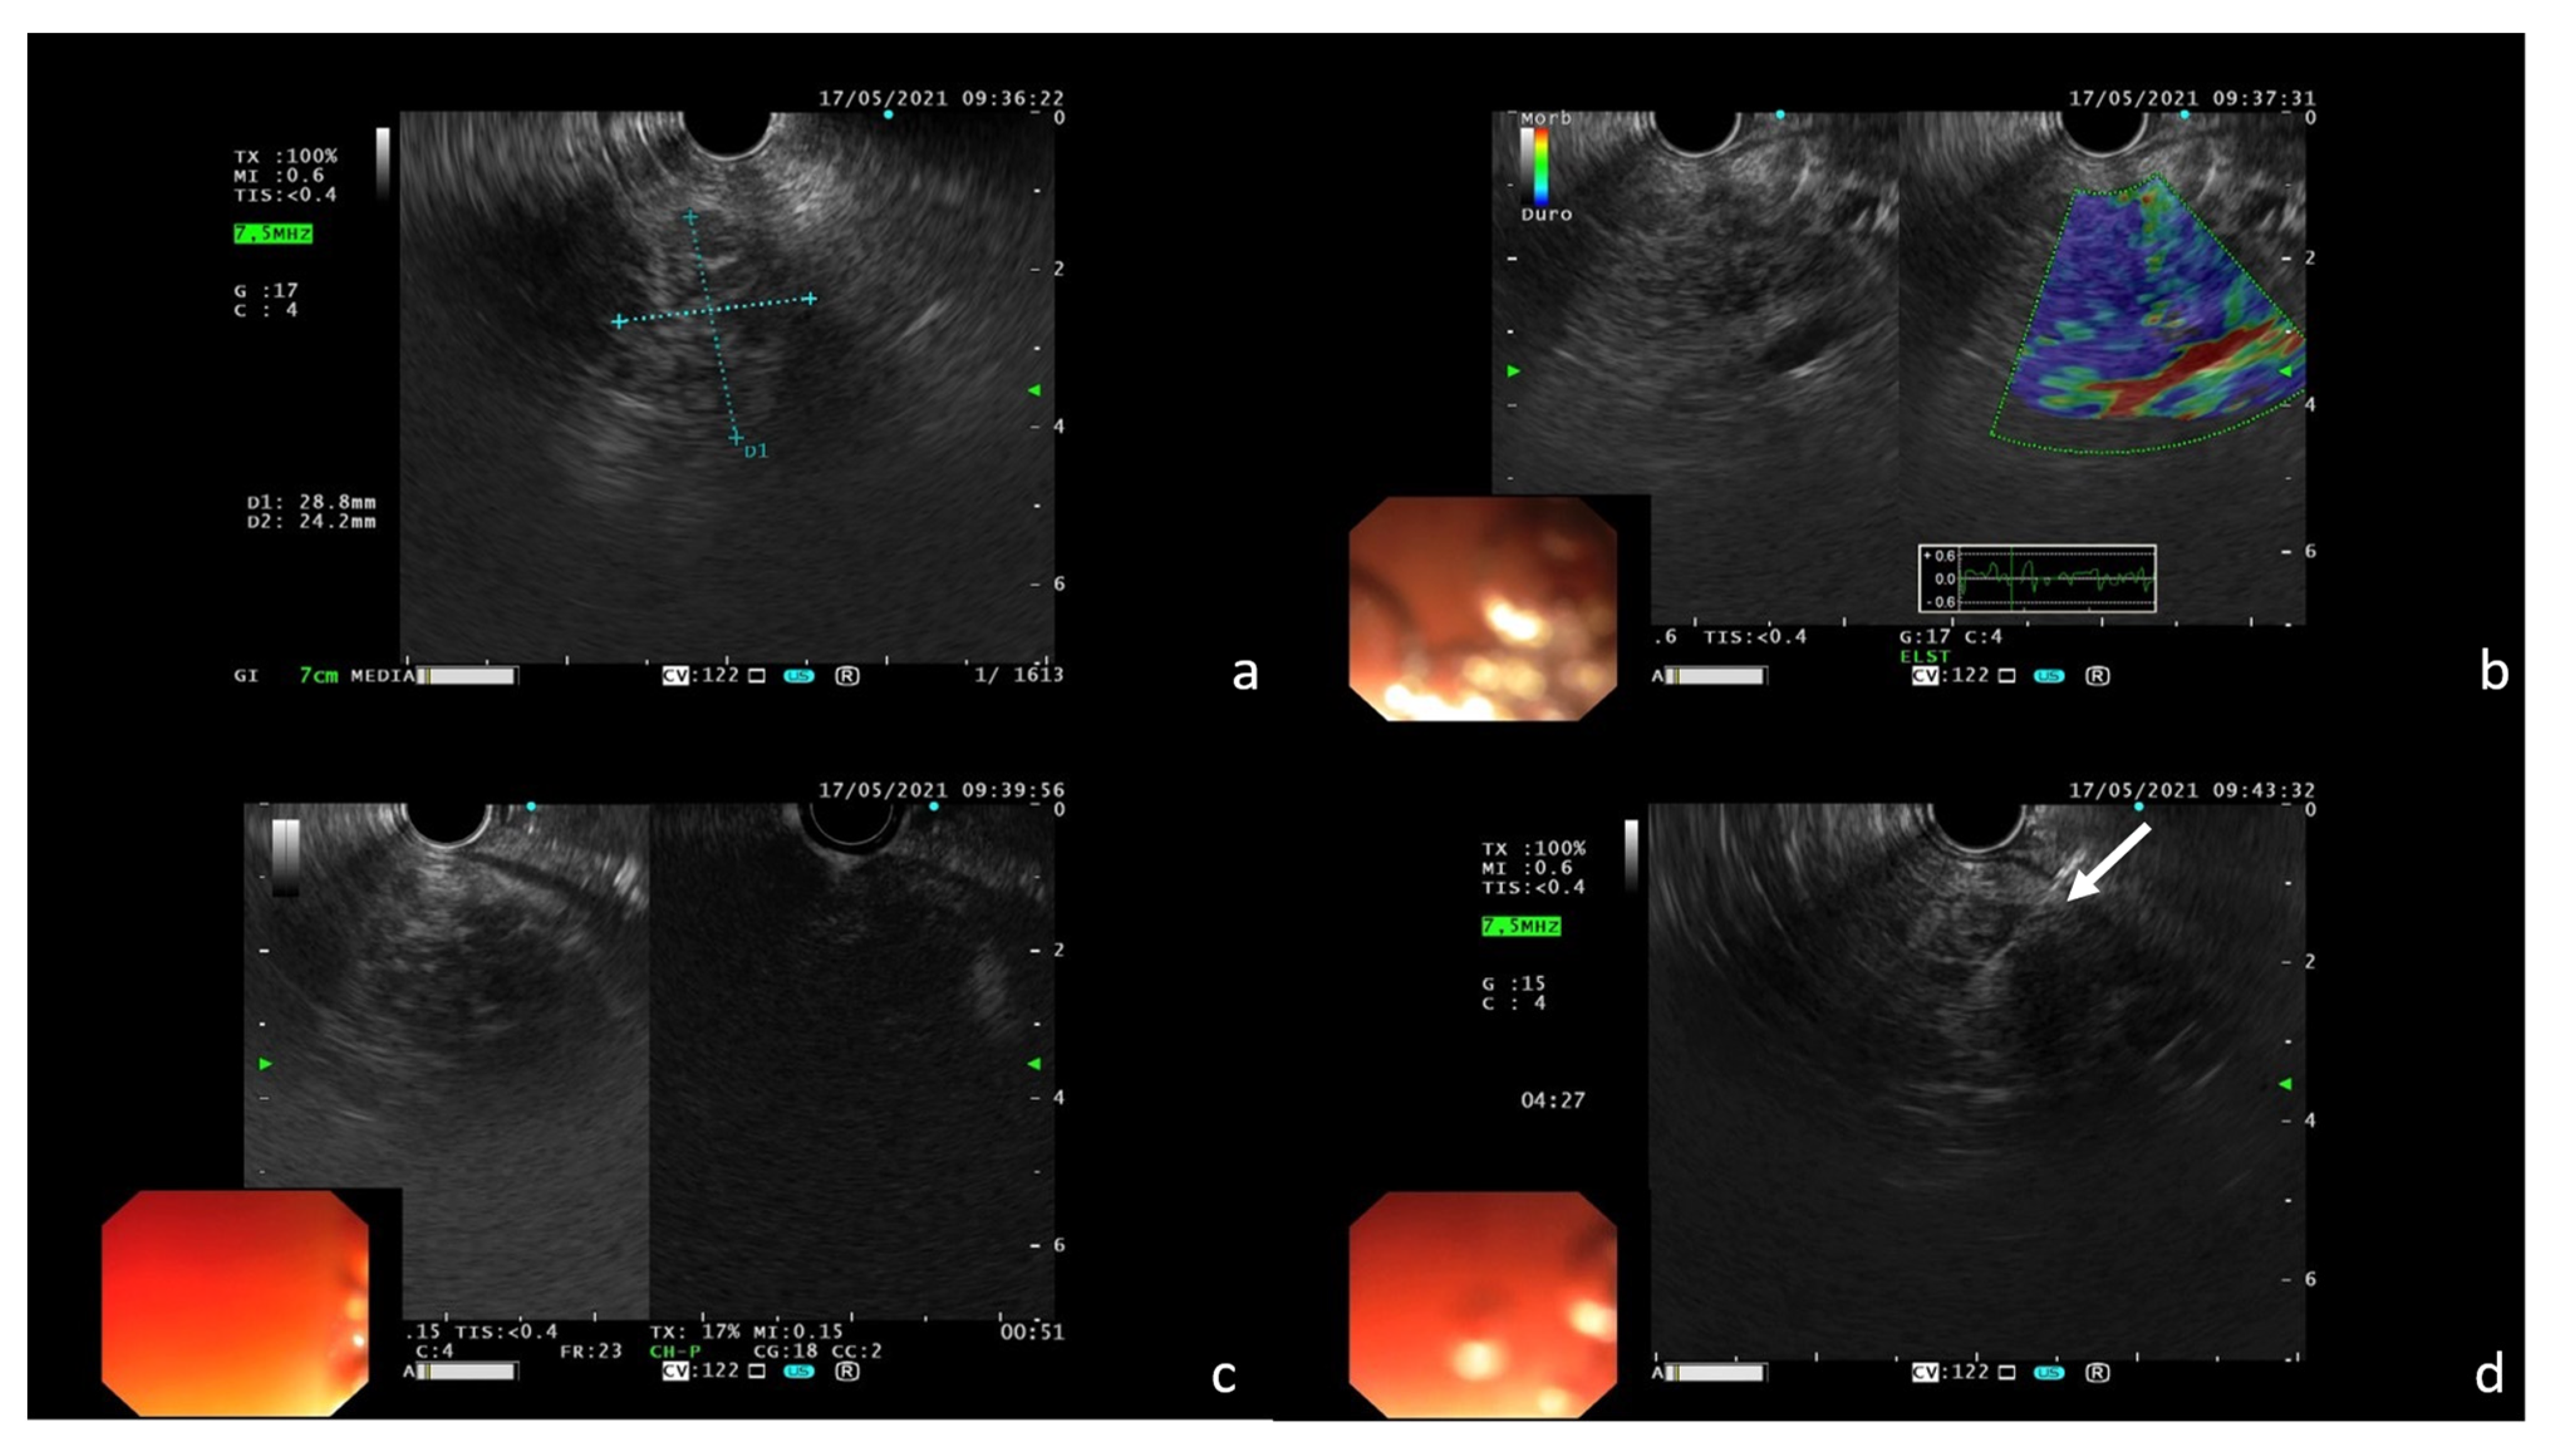

Stocky/Packed Pancreas: A Case of Focal Drug-Induced Acute Pancreatitis Mimicking Cancer

Di Serafino, M.; Ronza, R.; D’Auria, D.; Fiorentino, R.; Arundine, D.; De Leone, A.; Picascia, S.; Martino, A.; Crolla, E.; Campione, S.; et al. Stocky/Packed Pancreas: A Case of Focal Drug-Induced Acute Pancreatitis Mimicking Cancer. Tomography 2022, 8, 2073-2082. https://doi.org/10.3390/tomography8040174